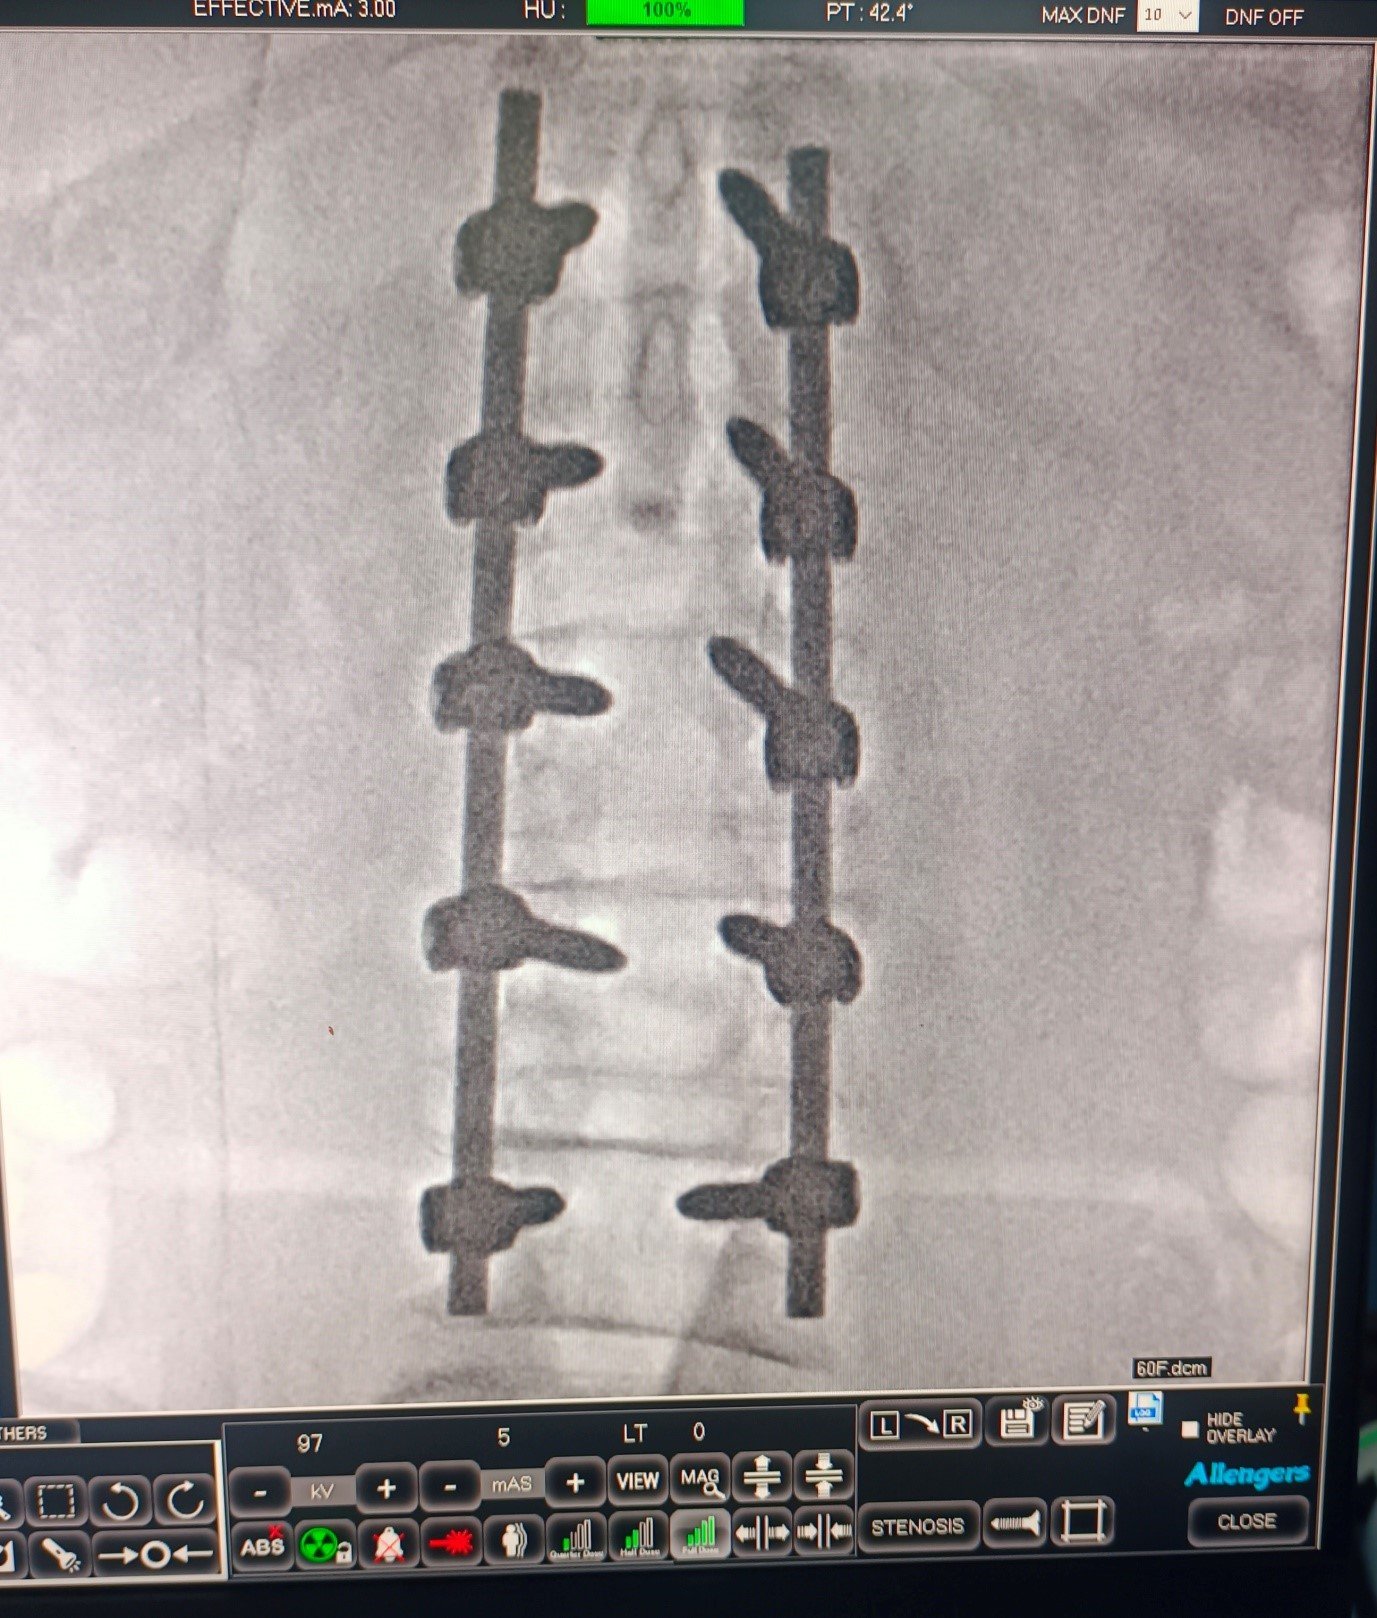

Special Cases Cervical Disc Prolapse with Spinal Cord Compression Condition:Cervical disc prolapse in which the herniated disc compresses the nerve roots and spinal cord, often associated with spinal cord edema. Symptoms:Neck pain, numbness in hands, weakness, difficulty in walking, and coordination problems. Treatment:Anterior Cervical Discectomy and Fusion (ACDF) – The…